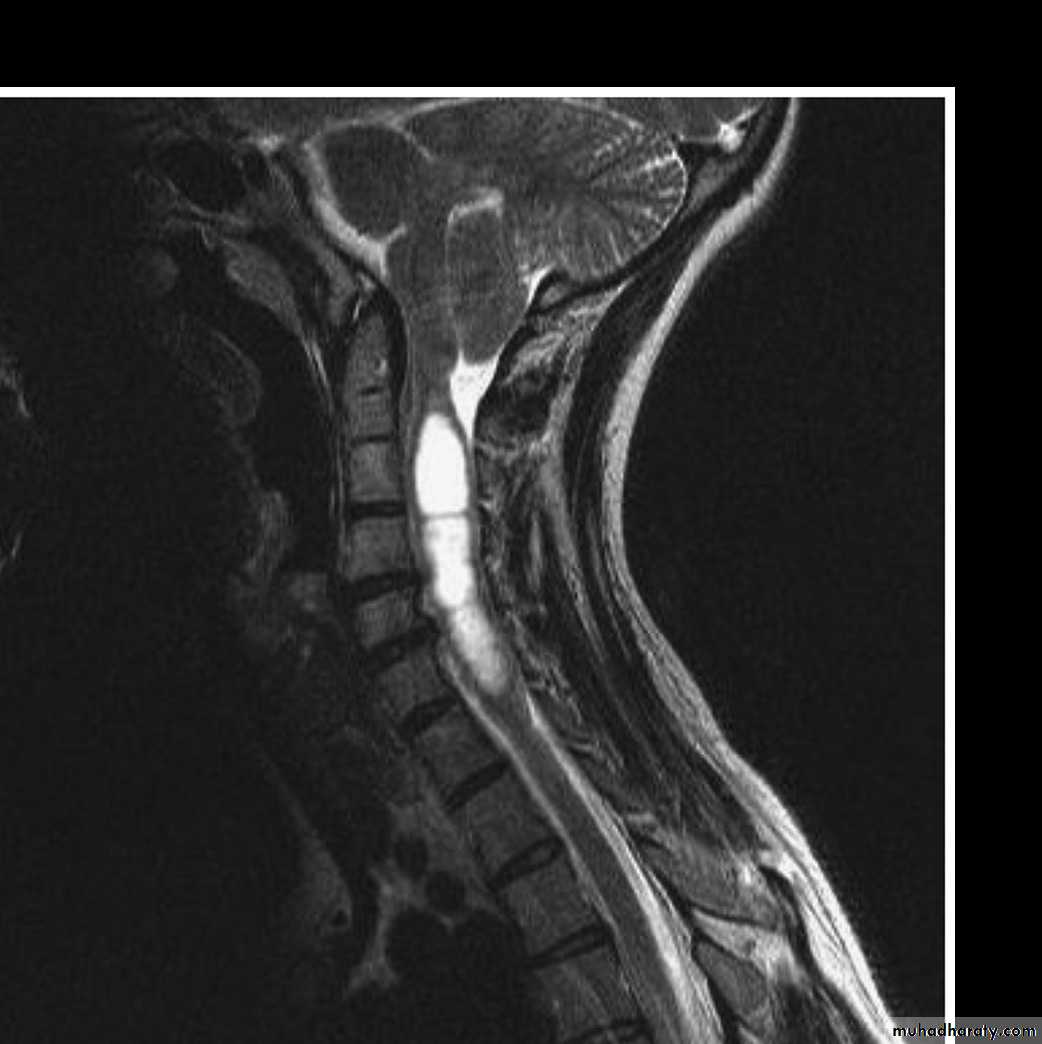

Syringomyelia:

Syringomyelia is a cystic dilation or fluid-filled cavity within the spinal cord that typically involves the cervical region, but may extend up into the brainstem or down to the conus.Causes:

1-Clinical symptoms follow the destructive path of the widening syrinx, which begins in the center and expands outward and longitudinally(central cord syndrome).2-flaccid weakness in lower cervical segments and corticospinal tract changes in the legs.

3-loss of pain and temperature sensation occurs in a capelike distribution due to injury of the decussating spinothalamic tract fibers.

4-the dorsal column still spared till late stage.

1-MRI of cervicothoracic spine with contrast is the investigation of choice which show cystic area filled with CSF.

2- MRI of brain and lumbosacral area should be done also to exclude chiari malformation and spina bifida.

consists of surgical drainage with restoration of CSF flow in patients with progressive symptoms.